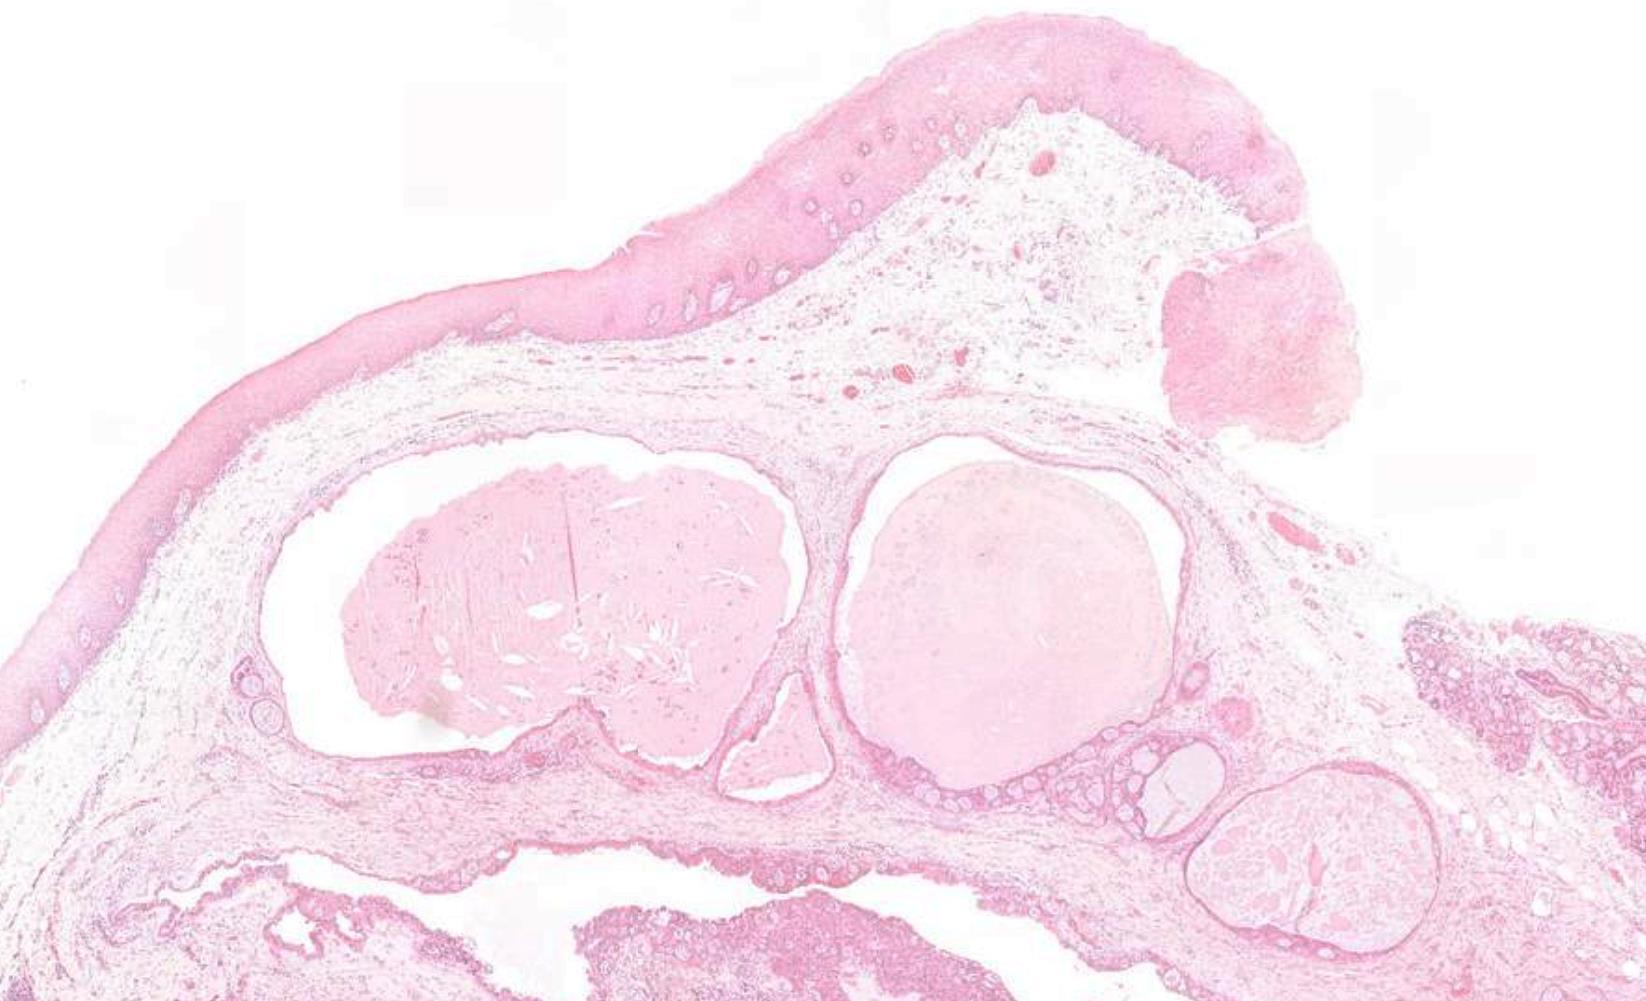

16-year-old, Female, Cyst Associated With Unerupted Lower Wisdom Tooth.

Case 5

Case 5- Salient points • Non-specific thin squamous epithelial lined cyst • No keratinisation, basal palisading • Largely uninflamed fibrous cyst wall • Location + histology

??

Case 5 Diagnosis

Dentigerous cyst

Common odontogenic cysts & tumours

• Dentigerous cyst • Radicular cyst • Odontogenic keratocyst • Orthokeratinised odontogenic cyst • Ameloblastoma • Radiology is a must- Location, relationship to tooth and nature of radiolucency can give diagnostic cluses